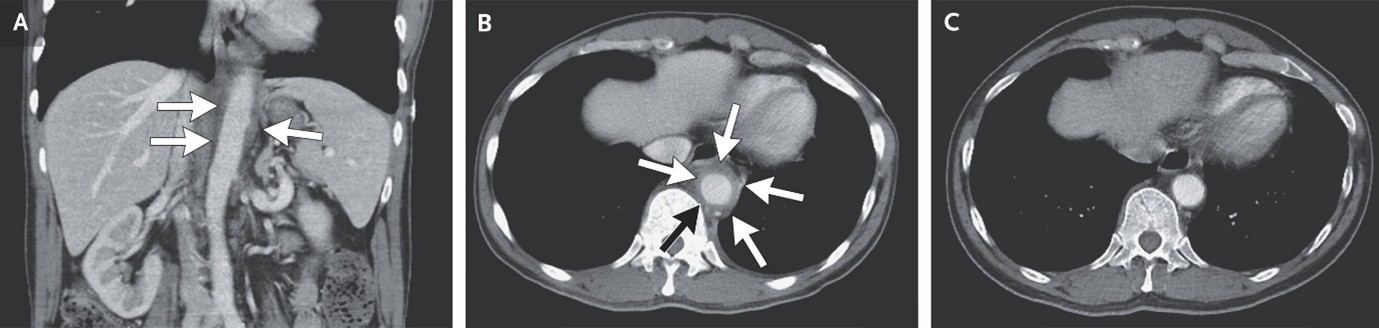

(4). Aortitis Due to Large-Vessel Vasculitis

Hsien-Tzung Liao, Published January 31, 2026, N Engl J Med 2026;394:588, DOI: 10.1056/NEJMicm2513456, VOL 394 NO. 6

Abstract

A 63-year-old man presented with a 3-month history of chest tightness, palpitations, and abdominal pain. Laboratory studies showed an elevated erythrocyte sedimentation rate and an elevated C-reactive protein level.